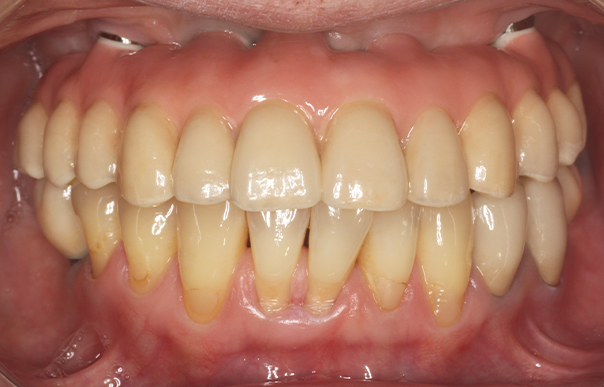

自分の歯を残しながら、噛みやすさと見た目を良くしたい 【オールオン6・義歯】